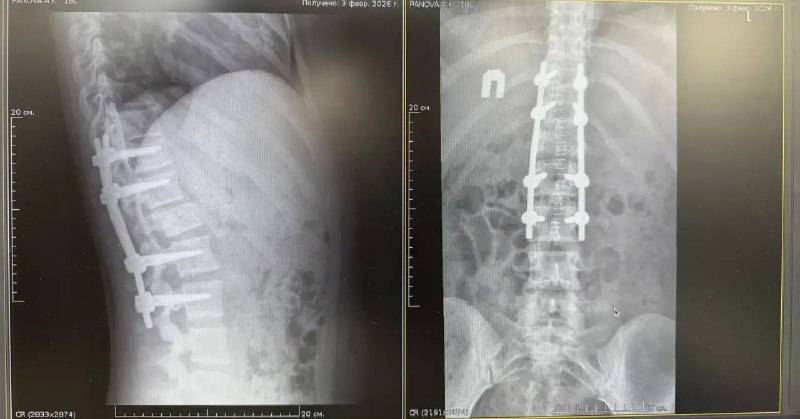

19 января во Владивостокскую клиническую больницу №2 из Арсеньева была экстренно доставлена молодая девушка с тяжёлой травмой — компрессионным переломом позвонка со стенозом позвоночного канала. Перелом сопровождался сдавливанием спинного мозга, что привело к парезу ног и нарушению функций тазовых органов.

После предоперационной подготовки нейрохирурги провели сложную четырёхчасовую операцию. Врачи устранили компрессию спинного мозга и стабилизировали позвоночник металлоконструкцией, предотвратив риск необратимых последствий. «Ключевую роль сыграло именно оперативное вмешательство. Мы сняли давление со спинного мозга и уже на вторые сутки начали раннюю реабилитацию», — отметил заведующий 1-м нейрохирургическим отделением Дмитрий Захаров.

Восстановление проходило поэтапно: в первые сутки пациентка находилась в реанимации для стабилизации состояния, уже на вторые сутки началась вертикализация, а к четвёртому дню она смогла самостоятельно передвигаться по палате.

К моменту выписки пациентка ходила самостоятельно, без дополнительных средств опоры. Сейчас она продолжает лечение амбулаторно.